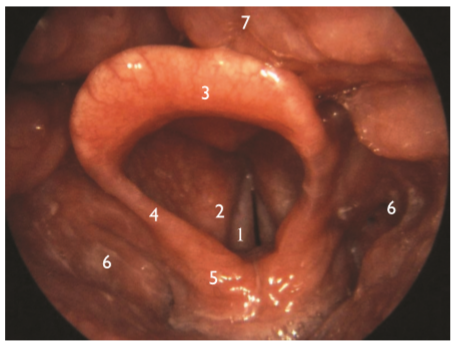

Fotoğrafta gırtlak yapısının anatomik yapılarını görmekteyiz. 2 no ile gösterilen kısım aşağıdakilerden hangisidir?

|

Ses telleri |

Dil köküdür |

Püriform sinüsler |

Yalancı ses telleri |

Epiglotu oluşturan dokular |

1.Ses telleri, 2.Yalancı ses telleri, 3-4-5.Epiglotu oluşturan dokular (yemek borusunu nefes borusundan ayıran doku) 6.Püriform sinüsler (gırtlağın yanlarında kalan alt yutağın yan duvarlarını oluşturan kısım) ve 7.Dil köküdür. Epiglot (3) ile dil kökü (7) arasında kalan bölgeye ventrikül adı verilir. Bu bölgelerdeki yapısal ve işlevsel bozukluklar yutma bozukluklarına neden olur (Logemann, 1998).